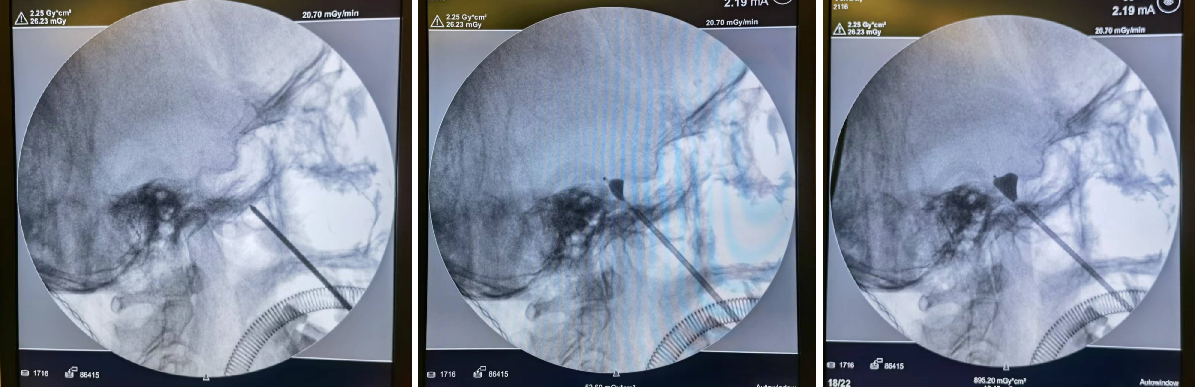

术中实时透视定位

患者全麻之后,团队在C型臂的透视定位下,迅速将穿刺针定位到患者三叉神经节所在的颅底卵圆孔,并将压迫球囊顺着针芯置入到卵圆孔附近的腔内,缓慢为球囊注入显影剂,利用球囊压力进行三叉神经节的机械性压迫,随后将显影剂释放后撤出球囊,手术顺利结束。